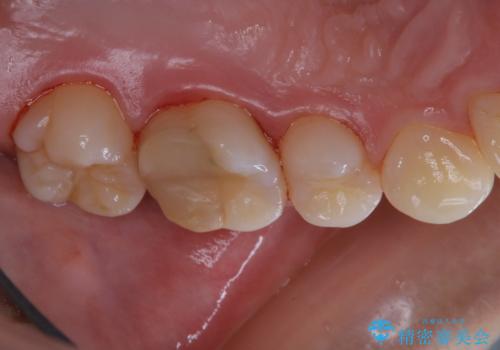

治療の前にPMTCできれいでツルツルな歯に

- 今後治療を進めていく予定で、まずはきれいにクリーニンングから行いたいとのことでした。PMTC60分コースを行いました。

PMTCを行う際には担当の歯科衛生士が、患者様1人1人の虫歯・歯周病などのリスク・ブラッシングスキルなどを確認します。

単なる磨き方の指導だけではなく、歯並びや歯肉の状態、ライフスタイルなどにより、患者様に適した歯ブラシや歯磨剤の選択をしたり、お口のお悩みについてのご相談も承っております。

定期的にPMTCでメンテナンスを行うことで、なにかあった時の早期発見につながります。

日々の磨き残しや唾液の成分などによりバイオフィルムや歯石はどうしても付着してしまいます。歯石や汚れを放置していると、そこで病原菌が繁殖す始めます。歯肉に炎症が生じると歯周病などの引き金となります。

そのため、2~3か月に1回は、歯科医院での専門的クリーニングをすることが大切です。